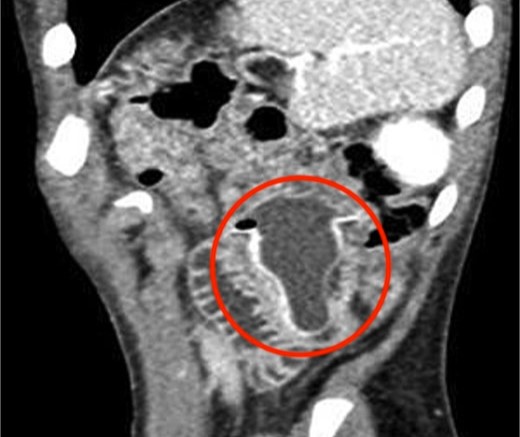

Các bác sĩ đã chụp X-quang dạ dày của bệnh nhi và phát hiện núm vú cao su chứa đầy chất lỏng mắc kẹt trong ruột non (phần giữa của ruột non).

Hình ảnh chụp cắt lớp cho thấy vật thể đó hiện rõ bên trong cơ thể cậu bé.